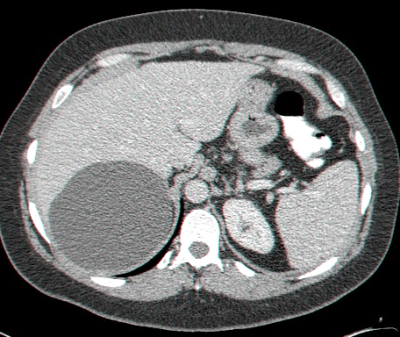

- בודדות (תצלום 19.10).

- מרובות (תצלום 20.10):

- נאופלסטיות (תצלום 21.10).

- מורסות (תצלום 22.10).

- טפיליות (תצלום 23.10).

- באולטרה-סאונד אפשר להדגים גוש כיסתי. האולטרה-סאונד הפך לאמצעי האבחנתי החשוב בכיסיות של הכבד (תצלום 24.10).

- בטומוגרפיה ממוחשבת ניתן לראות גוש בכבד (תצלום 25.10).